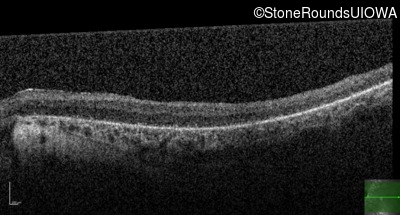

Optical Coherence Tomography - Right - 5/180

Exemplar / OCT Stack